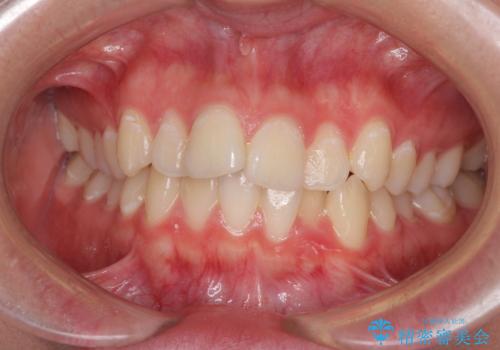

前歯のデコボコを改善 インビザライン矯正

- 口元のデコボコを気にして来院された患者様です。

前歯の捻れにより口元が閉じにくくなっていたため、歯列全体の側方への拡大と、歯と歯の間を少し削ってスペースを獲得することとしました。